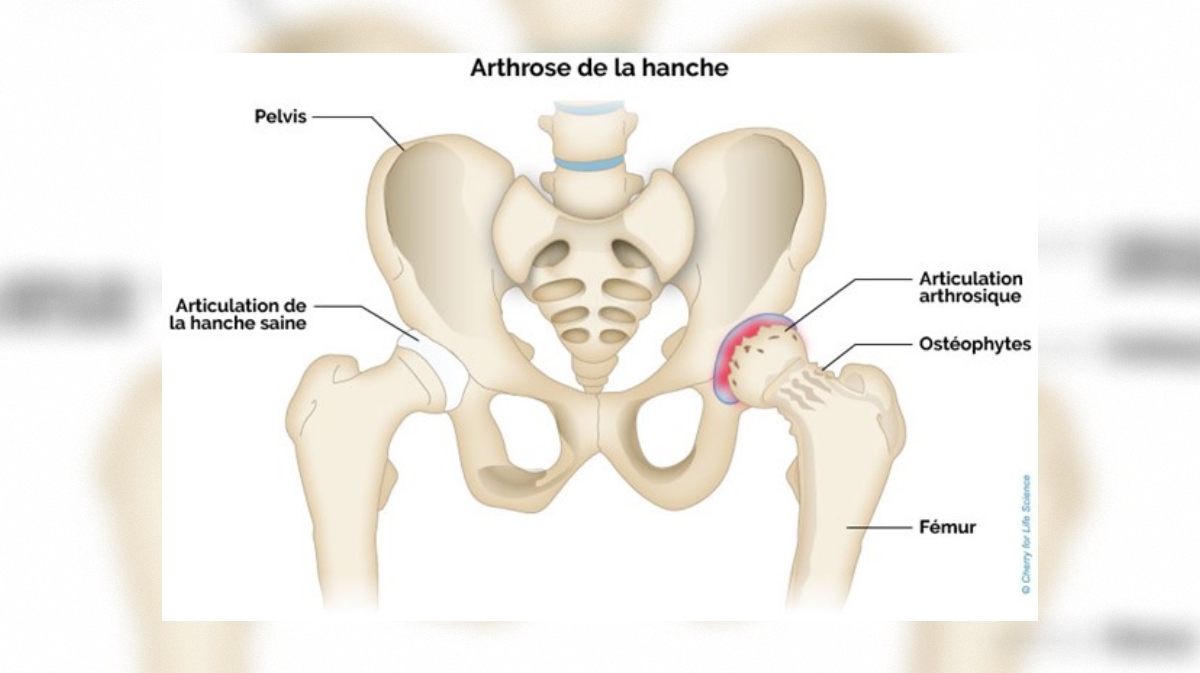

Arthrose : comprendre et agir

Guides pratiques sur l'arthrose du genou et de la hanche, et outil d'auto-évaluation rapide.